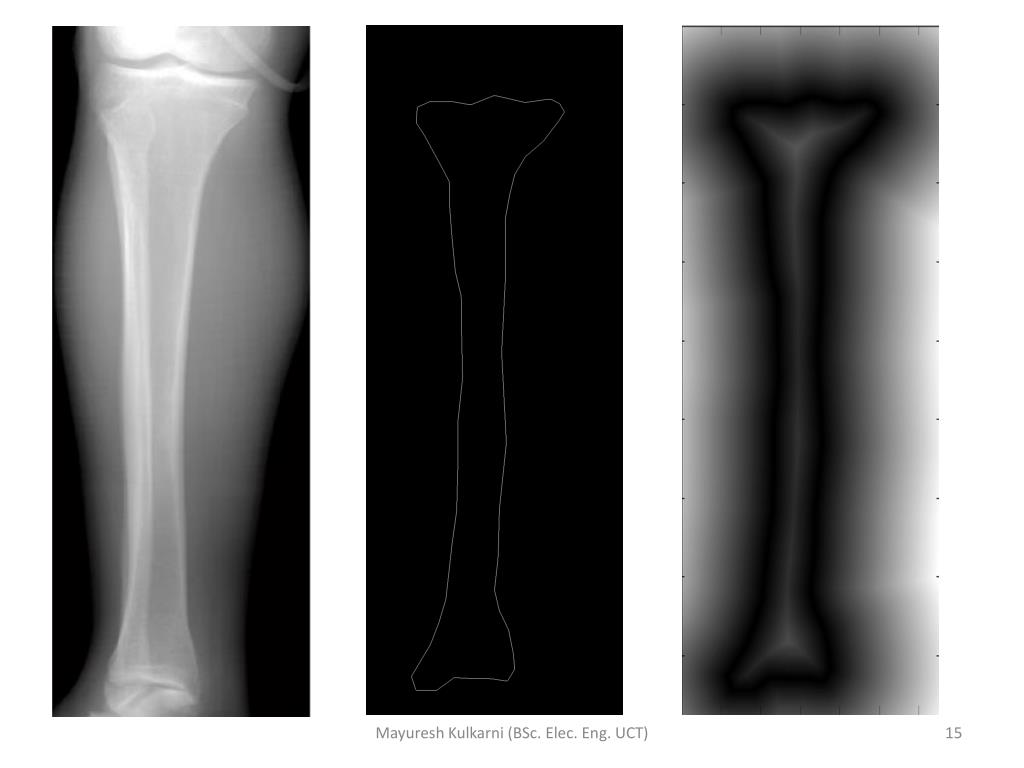

14. Defining the Error • Hand annotating the X-ray images • Distance transform • Comparing the ASM output to hand annotated images • Visual Check • Does the ASM track the bone? • Is it effective? Mayuresh Kulkarni (BSc. Elec. Eng. UCT)

15. Mayuresh Kulkarni (BSc. Elec. Eng. UCT)